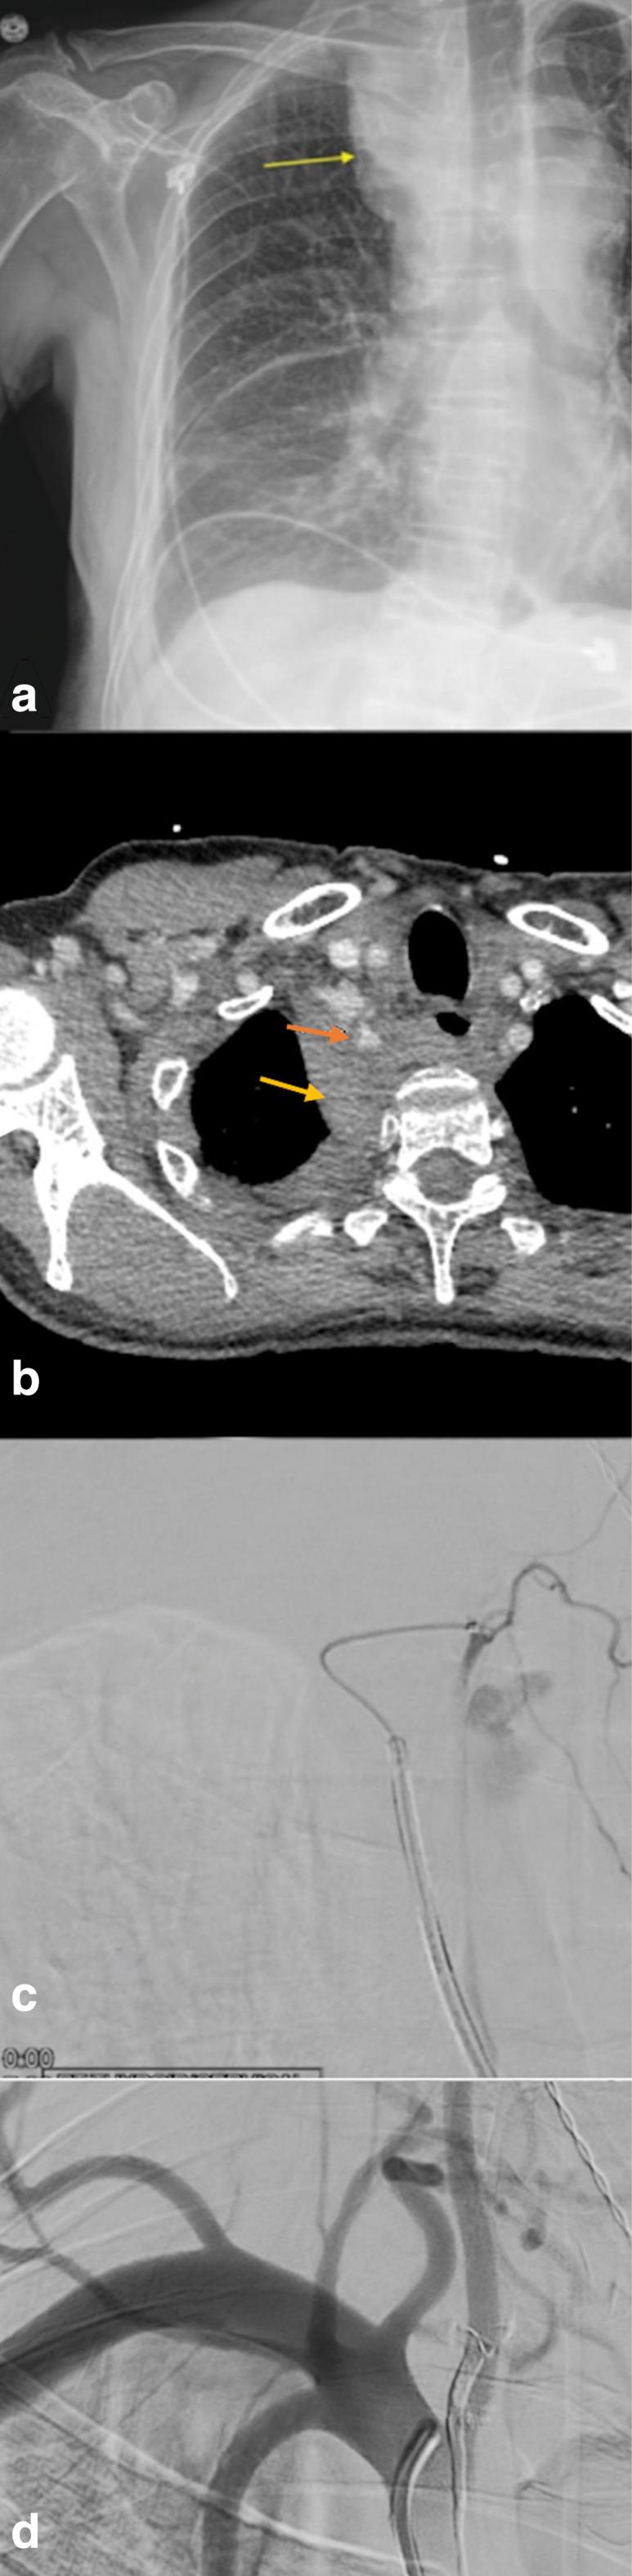

The transradial approach has gained popularity in the neuroendovascular field after several studies proved its low rate of hemorrhagic and vascular-related complications in both diagnostic and therapeutic procedures. This is a case of a patient who presented for flow diversion treatment of an incidental left carotid ophthalmic aneurysm. The procedure was uneventful. Post-operatively, the patient's neurological exam and vital signs were normal, however the patient complained of abdominal and chest pain that worsened when lying down and improved when sitting up. Radiologic diagnosis confirmed the presence of a thyrocervical trunk pseudoaneurysm which was completely obliterated with Onyx 18 embolization. Thyrocervical trunk pseudoaneurysm formation is a rare complication of the transradial approach. Shedding the light on these entities is essential as symptoms vary in severity and presentation and necessitate swift diagnosis and treatment.

在多项研究证明经桡动脉途径在诊断和治疗操作中出血及血管相关并发症发生率较低后,该途径在神经血管内介入领域已越来越受欢迎。本文报告一例因偶然发现的左侧颈内动脉眼动脉瘤而接受血流导向治疗的患者。手术过程顺利。术后,患者神经学检查及生命体征正常,但患者主诉腹部和胸部疼痛,平卧时加重,坐起时缓解。影像学诊断证实存在甲状腺颈干假性动脉瘤,通过使用Onyx 18进行栓塞,该假性动脉瘤完全闭塞。甲状腺颈干假性动脉瘤形成是经桡动脉途径的一种罕见并发症。了解这些情况至关重要,因为其症状的严重程度和表现各不相同,需要迅速诊断和治疗。